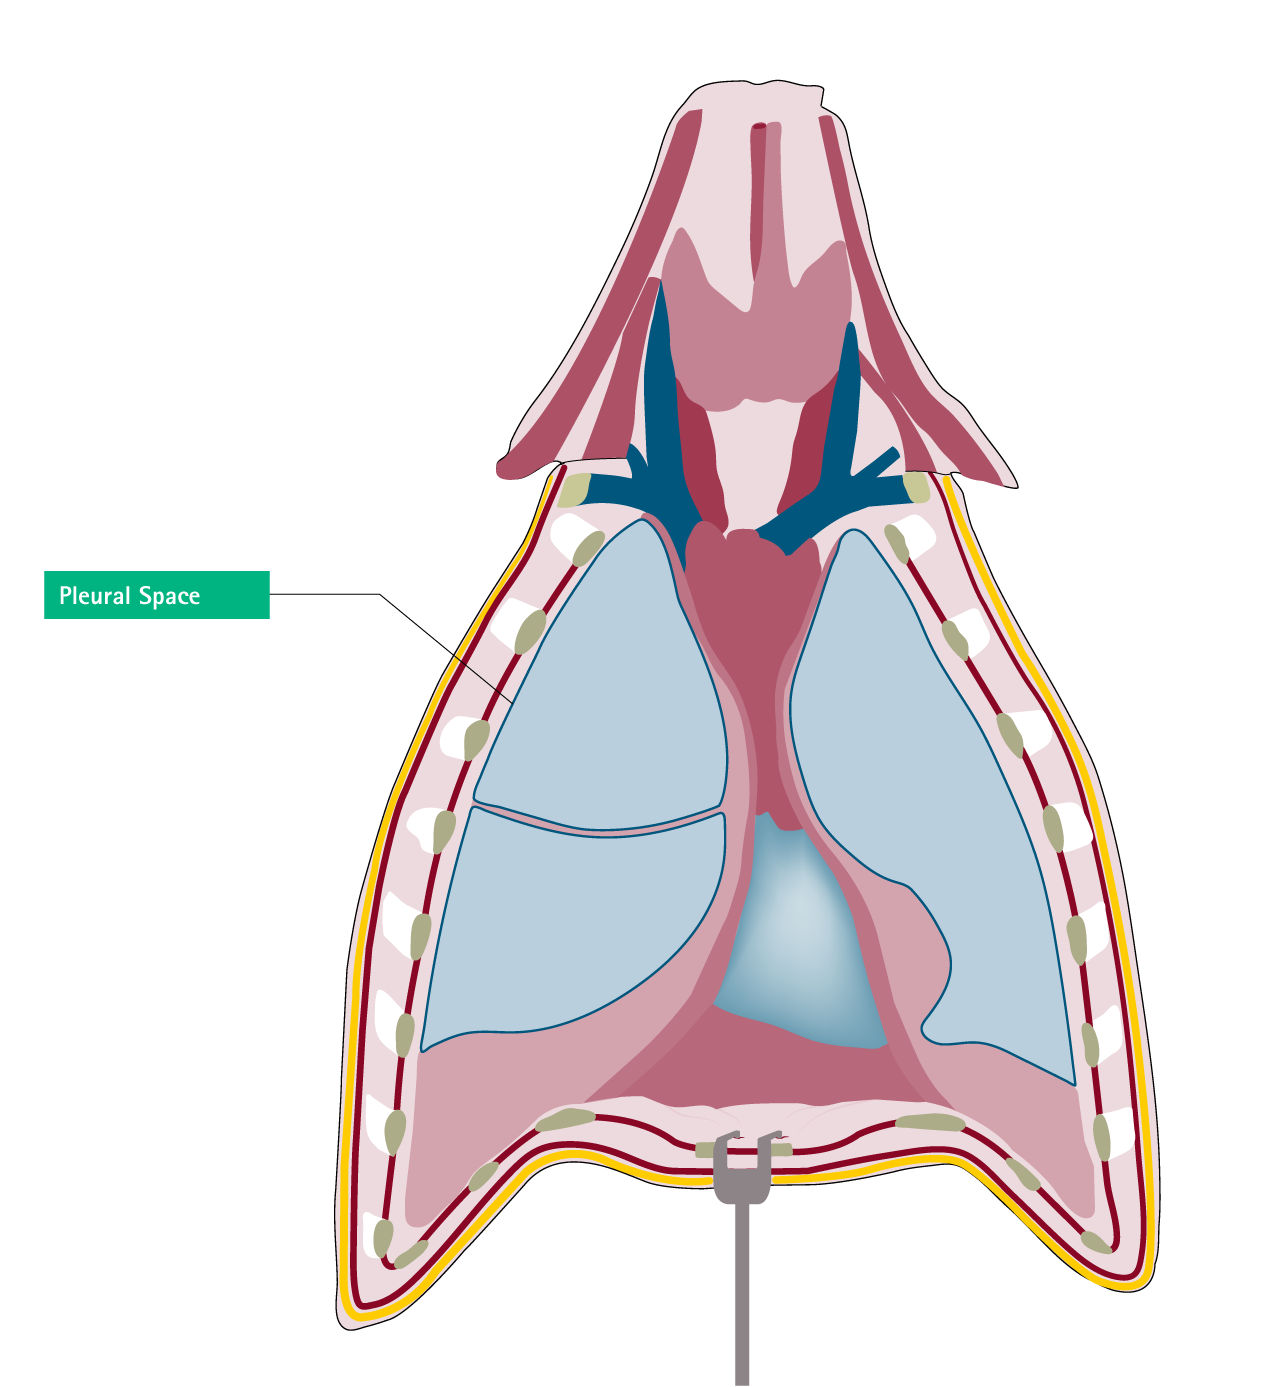

Extravascular Misplacement

Paersistent left sided superior vena cavaPleural space